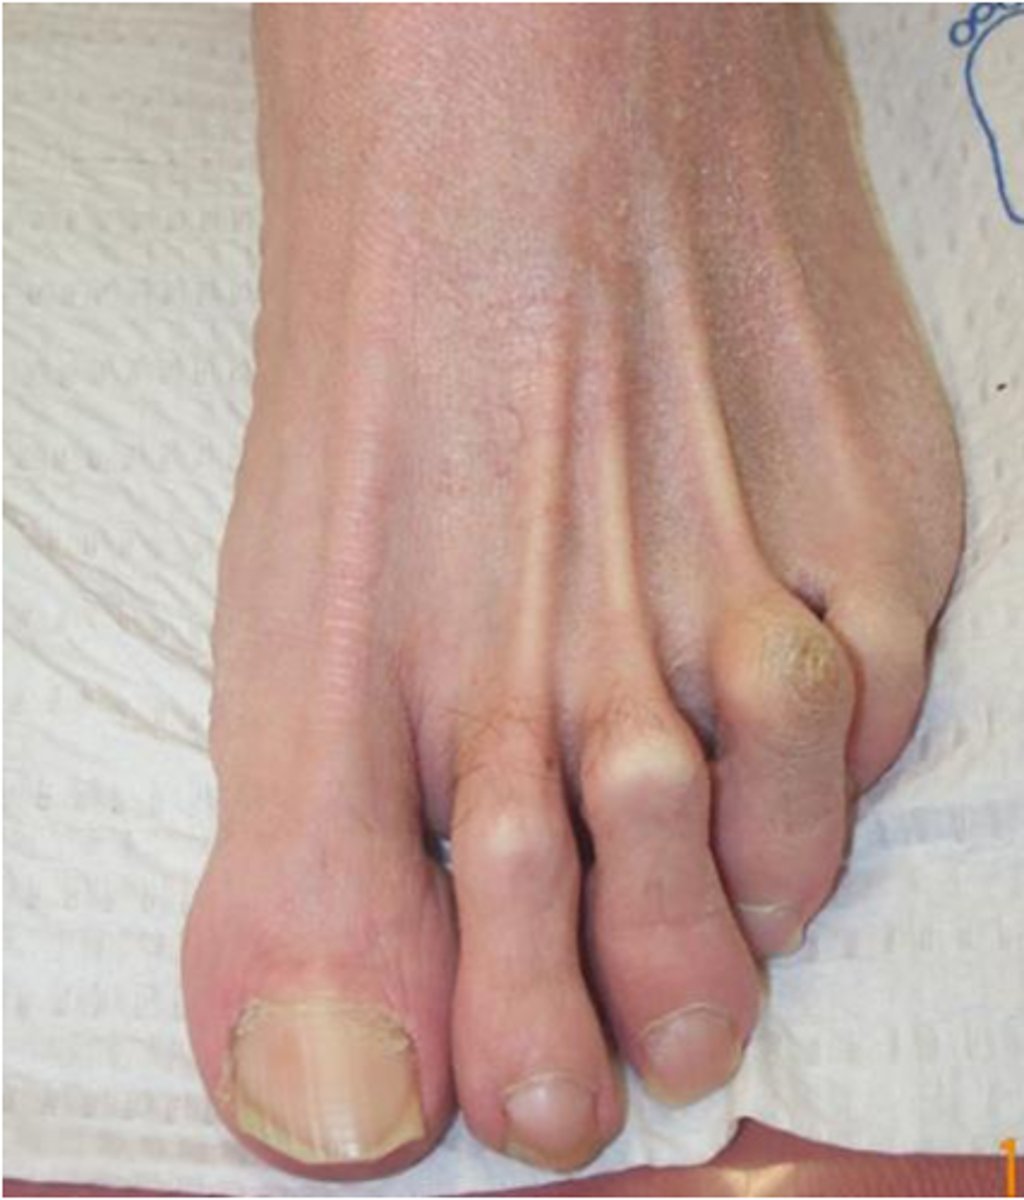

What is hallux valgus with bunion?

Lateral abduction of the great toe w/ medial deviation (adduction) of the 1st metatarsal

- the first metatarsophalangeal joint

Which joints are extended and flexed for protruding metatarsal heads with callosities?

extension at the metatarsophalangeal (MTP) joints

Explain the joints involved in hammertoes.

the proximal interphalangeal (PIP) joint is flexed, the metatarsophalangeal (MTP) joint is extended, and the distal interphalangeal (DIP) joint is also extended

Explain the joints involved in Mallet toe.

the distal interphalangeal (DIP) joint is flexed (bent downward), while the proximal interphalangeal (PIP) and metatarsophalangeal (MTP) joints are in a neutral or extended position

Explain the joints involved in Claw toes.

the Metatarsophalangeal (MTP) joint is extended, while the proximal and distal interphalangeal (PIP and DIP) joints are flexed